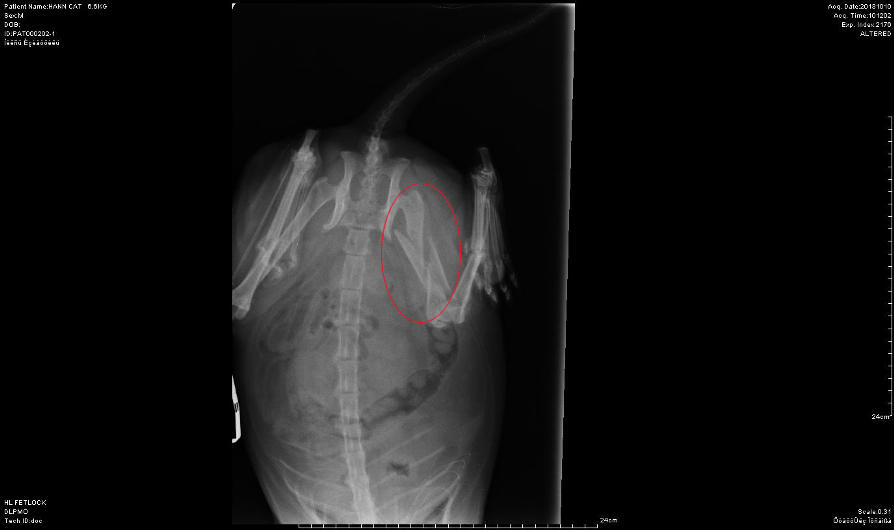

Also stellte man das Katerlie

für ein paar Wochen ruhig, in der Hoffnung, dass es doch irgendwie

von alleine ausheilen würde, leider war das nicht der Fall, wie die

Röntgenbilder 4 Wochen später zeigten, zudem humpelt Shakespeare

immer noch sehr stark und kann das Bein nicht belasten.